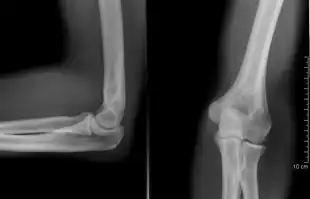

X-ray of ventral dislocation of the radial head. There is calcification of annular ligament, which can be seen as early as 2 weeks after injury.[29]